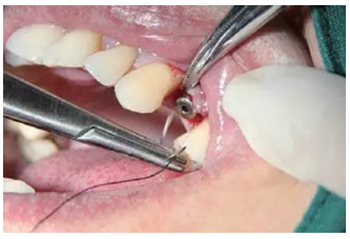

微創(chuàng)拔牙

微創(chuàng)拔除患牙,注意動作要輕柔,不能破壞骨壁。

圖10 微創(chuàng)拔牙

逐級備孔

戴上導(dǎo)板逐級備孔,然后植入種植體,旋入覆蓋螺絲。

注意導(dǎo)板的就位要準(zhǔn)確不晃動,備孔時(shí)應(yīng)充分冷卻。

圖11 導(dǎo)板上備孔并植入植體,a.戴上導(dǎo)板,逐級備孔;b.植入種植體,并旋入覆蓋螺絲